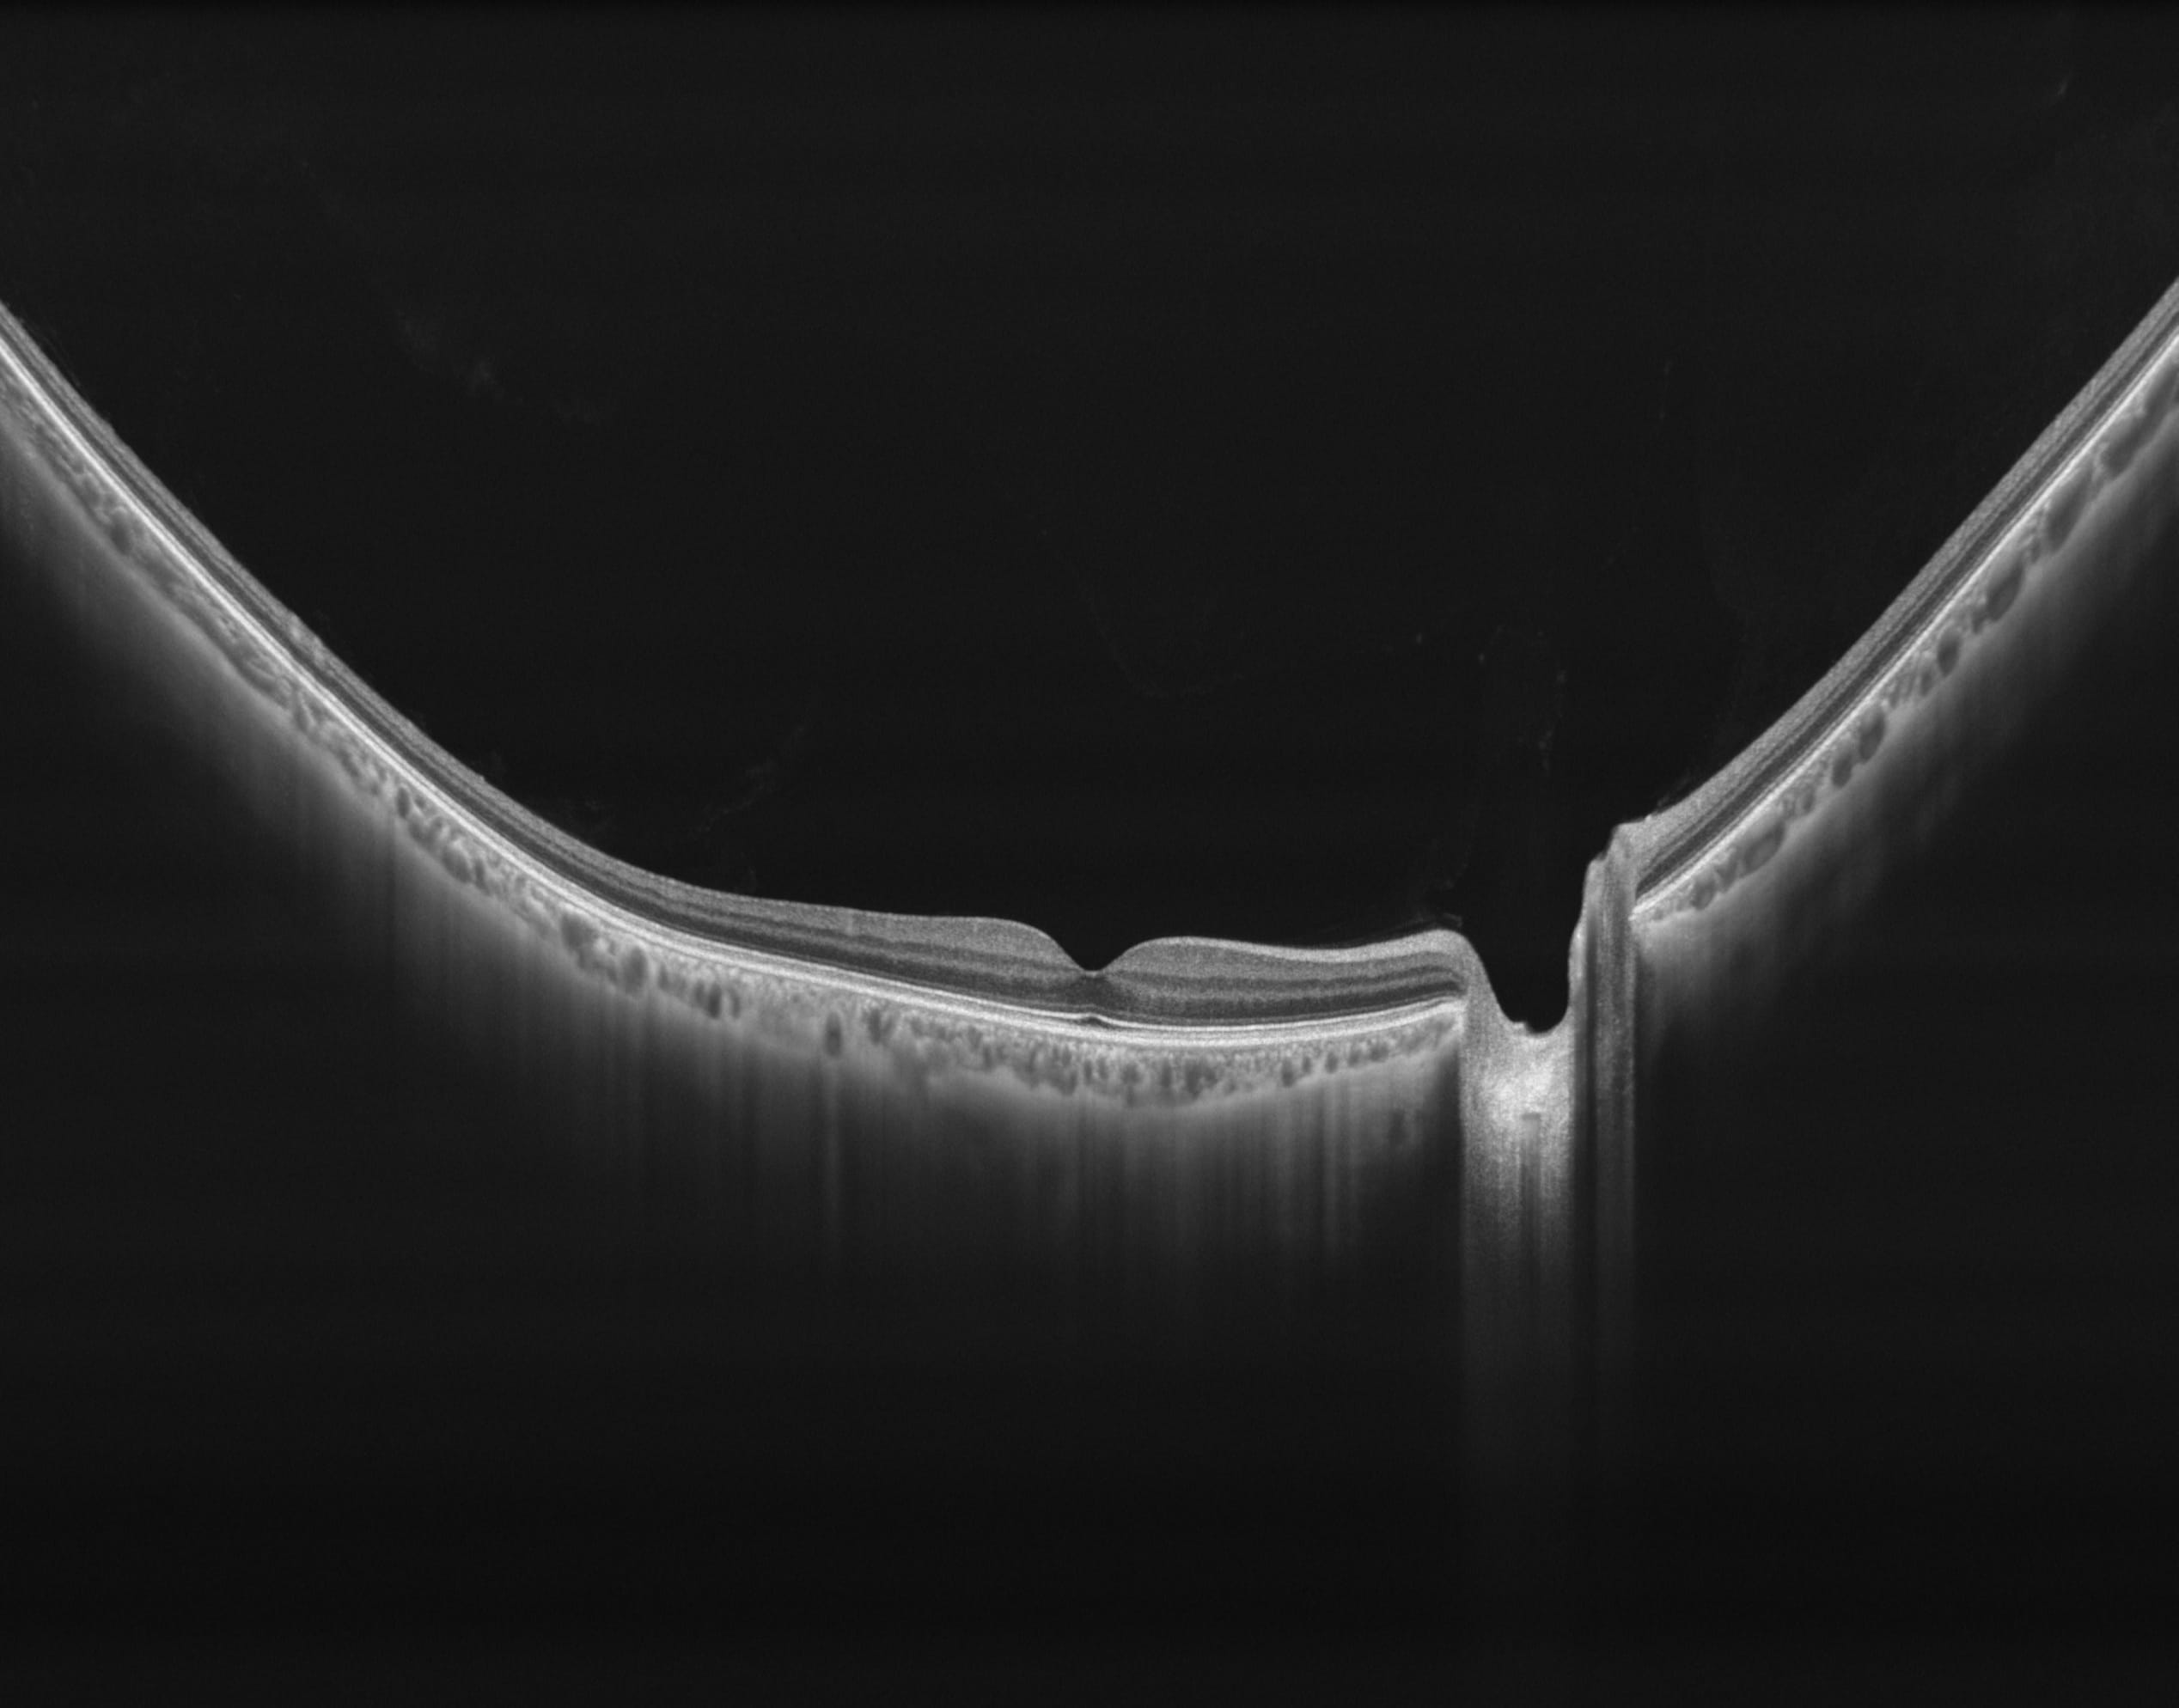

400kHz speed full-range swept-source OCT for anterior and posterior

- Full-Range wide-field Swept Source OCT

- Choroid OCTA with Quantification Parameters

- HD Anterior Scan with Anterior OCTA